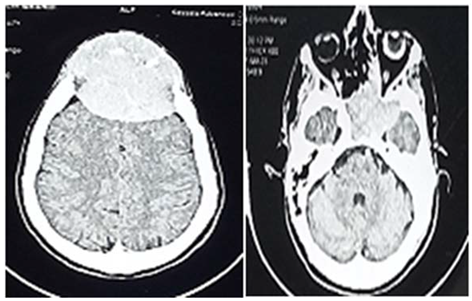

This is 54 years male, driver, and an otherwise healthy before, presented to neurosurgery emergency unit with history of few weeks headache and blurring of vision.

On examination; he was unwell, but conscious, there was Rt side weakness that power was grade 4 in both upper and lower limbs.

An urgent VP shunt anterior approach was done, after which the patient showed improvement concerning headache, but few weeks followed he developed unsteady gait and dizziness

When we counseled the patient and his family, the decision of surgery was made and the patient was prepared for excision of the cyst.

Operation: Through Rt para median craniectomy, intra operative; there was cyst containing oily like fluid and soft tissue, thus macroscopic excision was done.

Histopathology

Showed low grade oligodendroglioma.

Patient discharge home in a good condition, but presented with superficial wound infection consequently debridement was done.